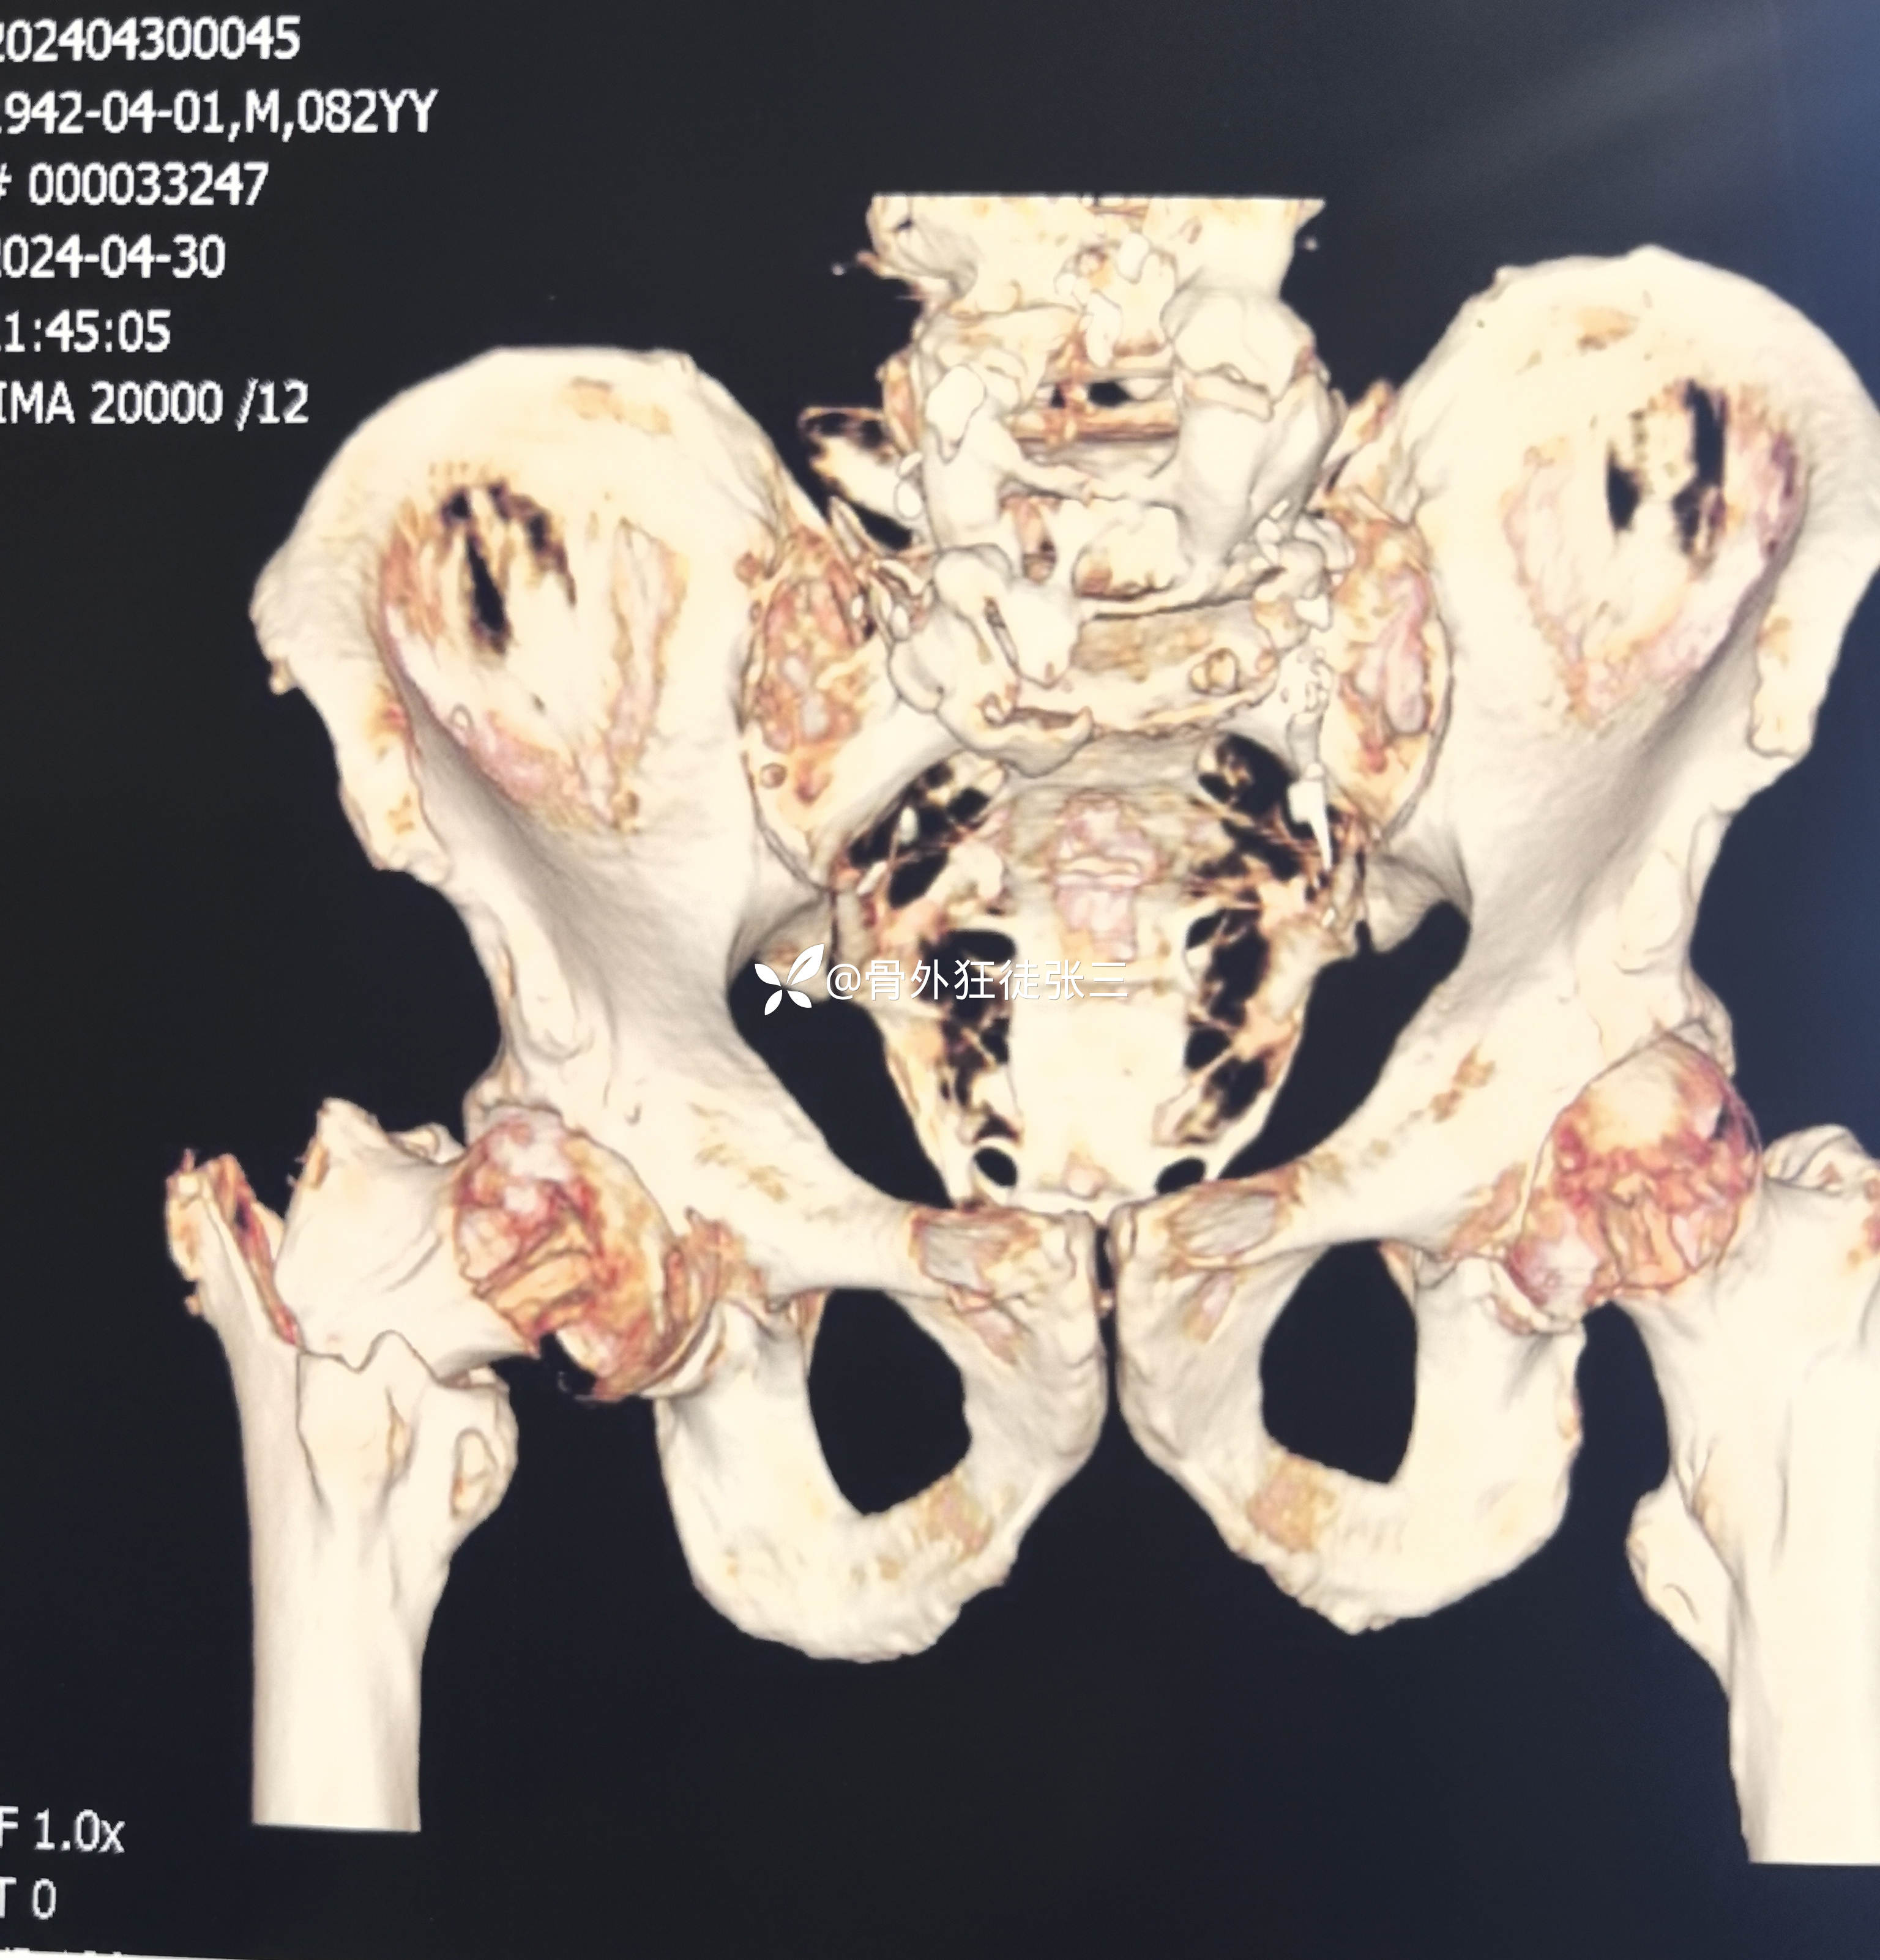

辅助检查:

右股骨转子间骨折